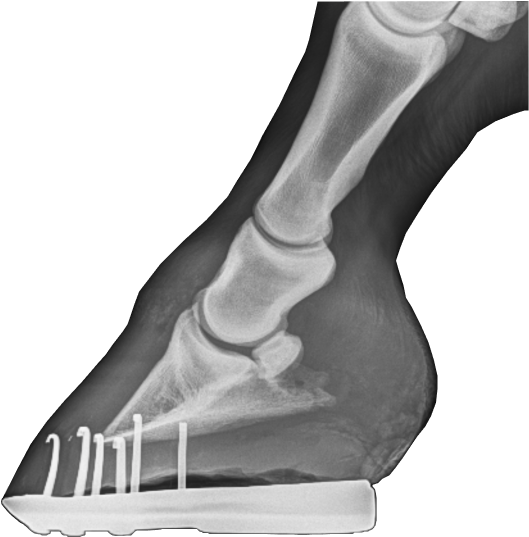

Оссификация хрящей копытной кости

Растяжение капсулы копытного сустава

Излишне длинный острый зацеп, мешающий нормальному перекату. Создает излишнее давление передней стенки на копытную кость